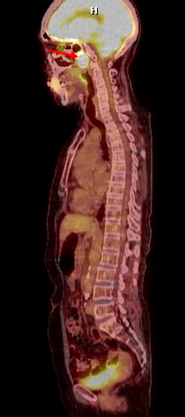

Dưới đây là một số hình ảnh minh họa giá trị của PET/CT trong phát hiện ung thư chưa rõ nguyên phát tại Trung tâm PET/CT -Bệnh viện Bạch Mai

Hình 1 mô tả kết quả ghi hình PET/CT của bệnh nhân Nguyễn Th. B., nữ, 52 tuổi. Gần đây thấy xuất hiện hạch cổ hai bên. Bệnh nhân đi khám và được nội soi vòm mũi họng thì không phát hiện thấy bất thường. X-quang, siêu âm đều cho hình ảnh bình thường. Sinh thiết hạch cổ có kết quả mô bệnh học là ung thư biểu mô không biệt hóa di căn hạch. Vì vậy bệnh nhân được chỉ định chụp PET/CT để phát hiện ung thư nguyên phát. Kết quả chụp PET/CT chỉ thấy hình ảnh ung thư vòm trái, di căn hạch cổ hai bên (tổn thương u vòm nằm dưới niêm mạc thành vòm trái nên không phát hiện được khi nội soi vòm).

Hình 1: Hình ảnh tổn thương nằm dưới niêm mạc thành vòm trái tăng hấp thu FDG mạnh (mũi tên đỏ). Nhiều hạch cổ hai bên tăng hấp thu FDG (mũi tên vàng). Kết luận: Hình ảnh ung thư vòm di căn hạch cổ hai bên.